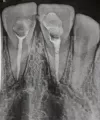

Двенадцать дней назад делала передние верхние зубы (был кариес), мне поставили светопломбы. Три дня назад проснулась с опухшей верхней губой, отек спал довольно быстро. Но со вчерашнего дня у меня над десной в районе носа шишка, болит, даже больно улыбаться, части носа тоже больно, нажимать больно, отдает в зуб. Но когда стучишь по зубам — не больно.

По Вашим симптомам можно сказать, что у вас обострение хронического воспаления (периодонтит). Причина, как правило, некачественное эндодонтическое лечение. Обратитесь срочно к стоматологу-терапевту, в противном случае Вы можете серьёзно повредить и даже потерять зуб